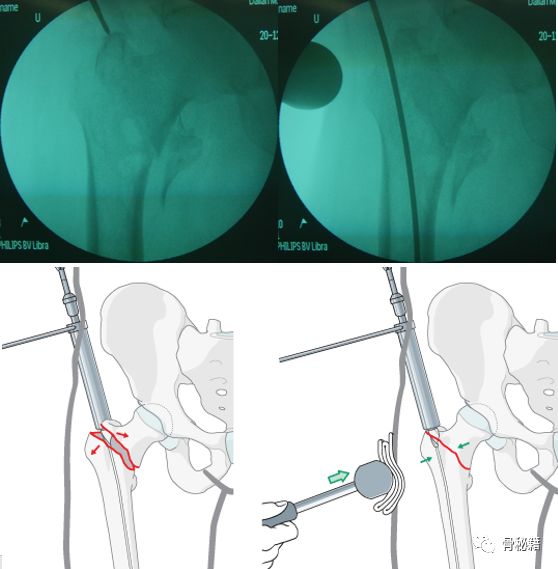

1.应用螺纹导针,植入到偏前方的皮质 直达内侧的骨折块

2.将该导针套上一个套筒直达骨皮质,套筒上夹kocher钳,远端连接T把手

3.下面就是复位了,将带螺纹的导针经过T把手向外侧拉,同时向内侧推kocher钳和所夹的套筒。这样一个进一个出,就完成了复位。

4.这种情况下就可以在复位加压的情况下完成骨折的扩髓和固定了